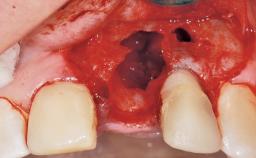

A 30-year-old female patient had lost tooth 21 and was referred to our clinic for consultation and treatment. Due to advanced apical infection, tooth 21 had been extracted two months earlier at another clinic and an acrylic-resin tooth had been bonded to the adjacent teeth. The patient desired implant treatment to avoid any damage to the adjacent natural teeth. While the patient had no history of any systemic disorder, she was a heavy smoker and exhibited medium to advanced periodontitis in the entire jaw. After the initial treatment to achieve a pocket probing depth of less than 4 mm and no bleeding on probing, a decrease in the height of the papillae mesial and distal to the extraction site and overall gingival recession were observed.

Bone Augmentation Horizontal|Staged

Augmentation Materials Autogenous chips|Membrane

Soft Tissue Grafting Simultaneous

Bone Volume Deficient horizontally, requiring prior grafting